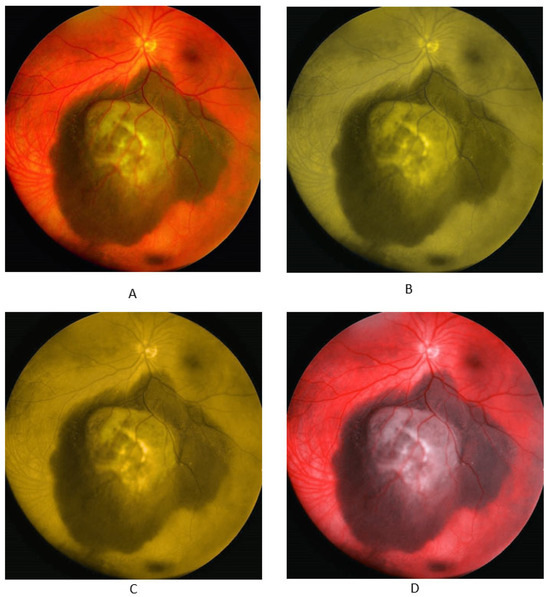

3.2. Nevus Images